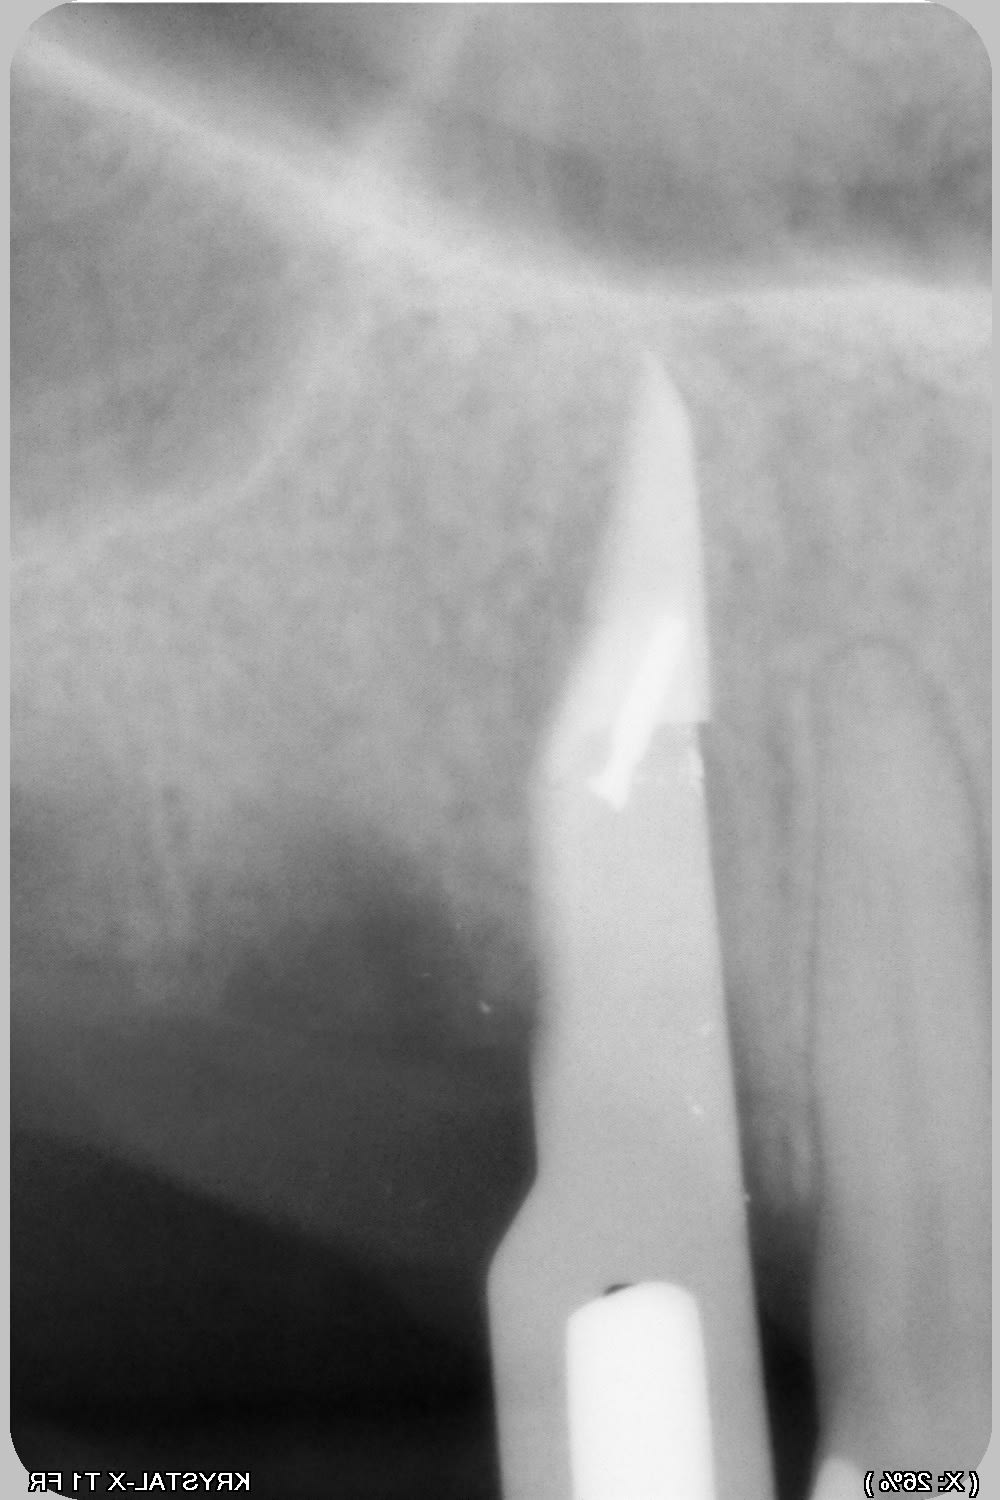

de nouveau lame 15, sonde 17, luxotome...et ça vient....mince il reste la pointe....je ne veux pas risquer de l'envoyer plus haut donc je me dis qu'elle ne gênera pas.

020 ef3xxb - Eugenol

025 vjxi28 - Eugenol